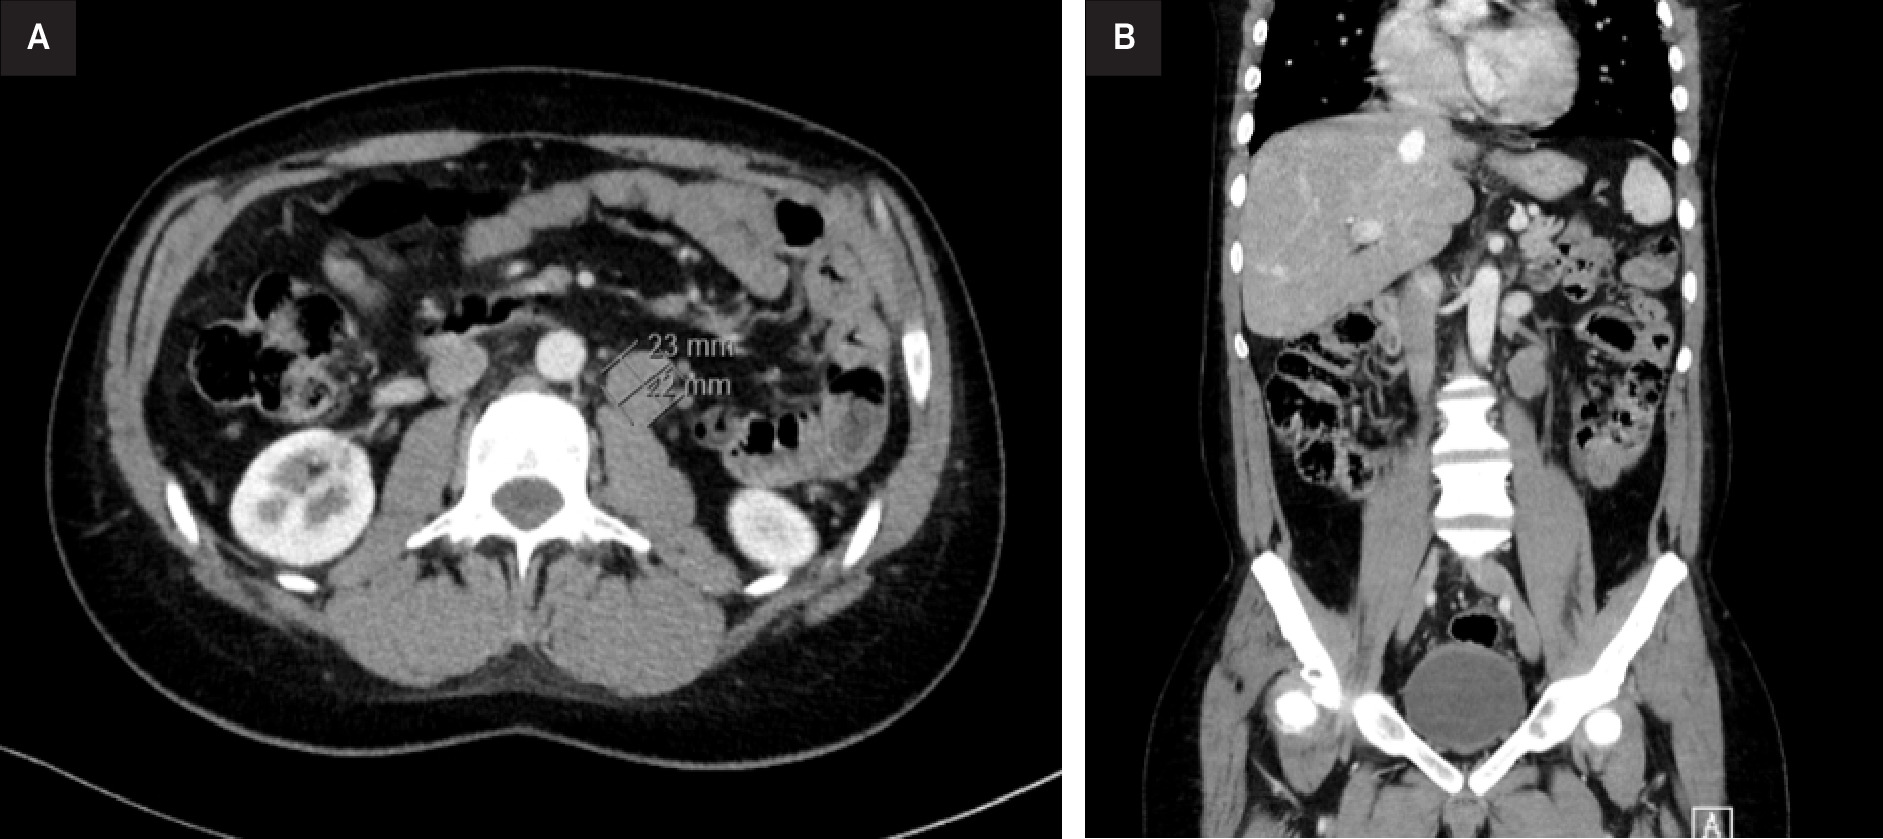

The patient was comfortable at rest, without any pain, fever, weight loss, or other symptoms. Examination revealed a mass on his left testicle without inguinal or other palpable adenomegalies. A scrotal ultrasonography revealed a well-defined left testicular solid tumor, with heterogeneous echogenicity. Following admission, routine blood work showed a mildly elevated white cell count at 12.4 × 109/L and a β-human chorionic gonadotrophin slightly elevated at 5.98 mIU/mL. All other blood markers, including tumor marker levels of α-fetoprotein and lactic dehydrogenase, were within normal range. A thoraco-abdominal-pelvic tomography (CT-TAP), performed in the same month, revealed a retroperitoneal left para-aortic lymphadenopathy, located below the renal vein, measuring 20 mm, suggestive of metastatic spread. A large heterogeneous expansive lesion was identified (Figure 1).

During the surveillance period, a follow-up CT-TAP at 4 months revealed, of oncological significance, a retroperitoneal lateroaortic lymphadenopathy, with the largest node measuring 23 × 22 mm, suspicious for nodal metastasis.